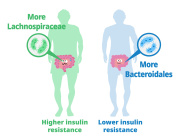

Previous analyses of gut microflora revealed associations between specific microbes and host health and disease status, genotype and diet.

This approach has allowed us to define two lists of 95 intestinal biomarkers of human aging. We further show that this list can be reduced to 39 taxa that convey the most information on their host’s aging.